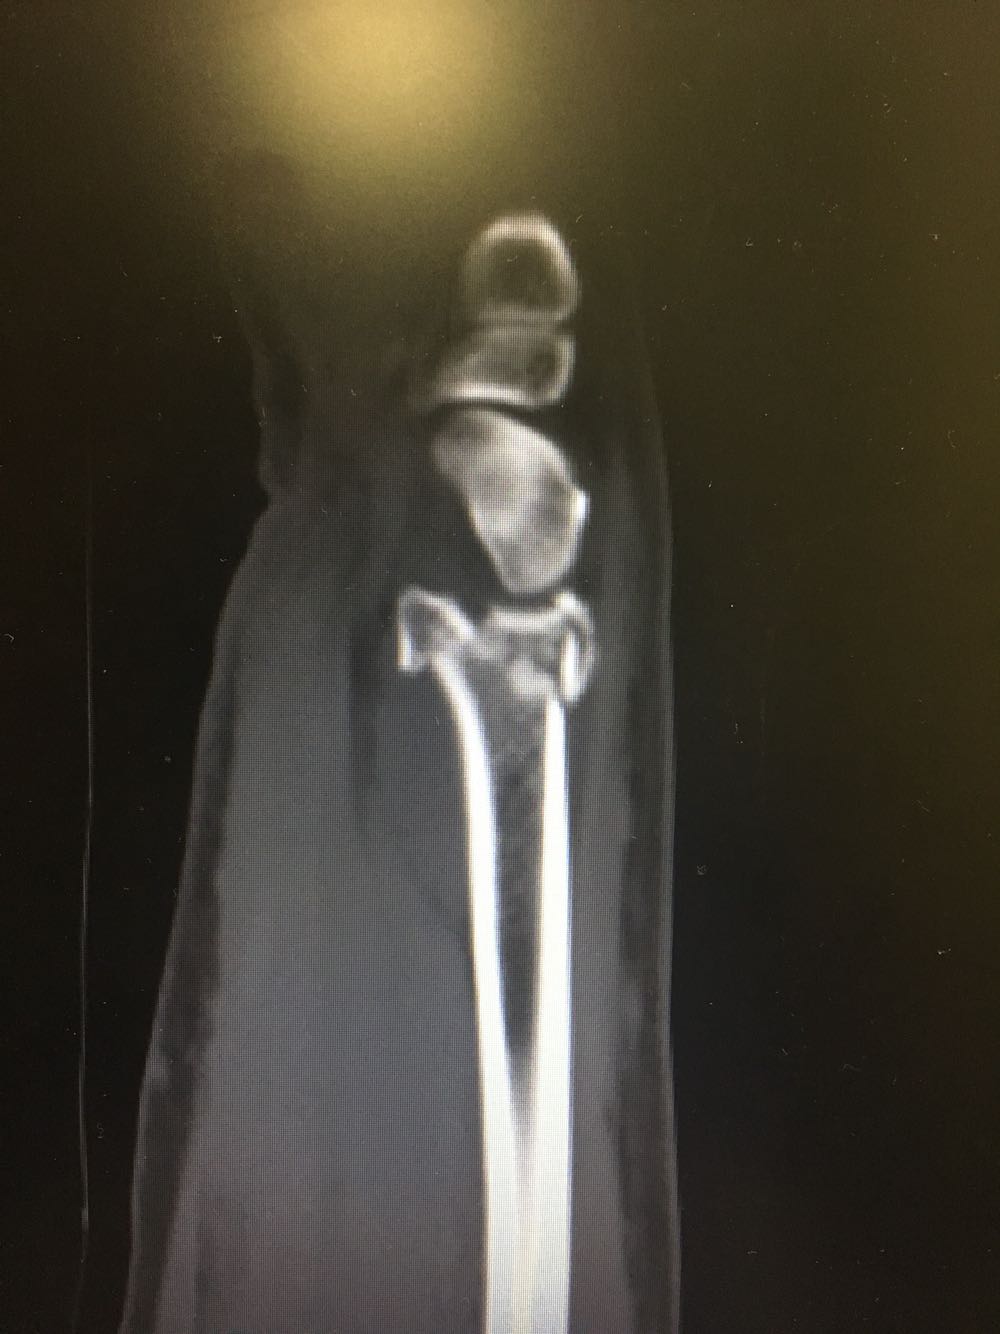

右尺桡骨双骨折

患者,男性,52岁 主诉:摔倒后右腕关节活动受限2天 现病史:患者于2天前于不慎,身体向右摔倒,右手掌着地后突感右侧腕部剧烈疼痛,后出现肿胀伴活动障碍,否认头晕头痛、恶心呕吐等不适,未见淤斑淤点,遂至我院就诊,查X片示:右侧桡骨远端及齿骨茎突骨折,现为进一步诊治收治入院,发病以来,神清,精神可,胃纳夜眠可,二便无殊,体重无明显变化。

查体:右手腕部压痛明显,伴活动受限,其余部位压痛不明显,患侧手指感觉及运动正常。 辅检:腕部CT

诊断:尺桡骨远端骨折(右侧) 治疗:完善术前检查后手术内固定